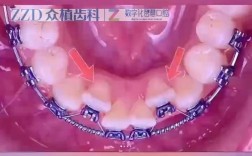

- 纠正磨牙扭转:对于上颌磨牙(尤其是第二磨牙)的颊舌向扭转,横腭杆可施加持续、轻柔的扭转力,配合其他矫治器(如方丝弓)使牙齿旋转至正常位置。